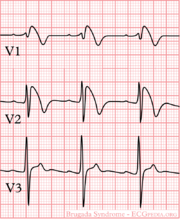

| 09:21, 9 October 2012 | Brugada.png (file) |  |

29 KB | 1 | |

| 09:22, 9 October 2012 | Brugada syndrome type1 example3.png (file) |  |

63 KB | 1 | |

| 09:24, 9 October 2012 | Brugada syndrome type1 example4.png (file) |  |

364 KB | 1 | |

| 09:25, 9 October 2012 | Brugada syndrome type1 example5.png (file) |  |

364 KB | 1 | |

| 09:25, 9 October 2012 | Brugada syndrome type1 example1.png (file) |  |

370 KB | 1 | |

| 09:26, 9 October 2012 | Brugada syndrome type2 example1.png (file) |  |

363 KB | 1 | |

| 09:26, 9 October 2012 | Brugada syndrome type1 example2.png (file) |  |

348 KB | 1 | |

| 09:29, 9 October 2012 | Brugada syndrome type2 example2.jpg (file) |  |

677 KB | 1 | |

| 09:31, 9 October 2012 | Brugada syndrome type1 example6.jpg (file) |  |

970 KB | 1 | |